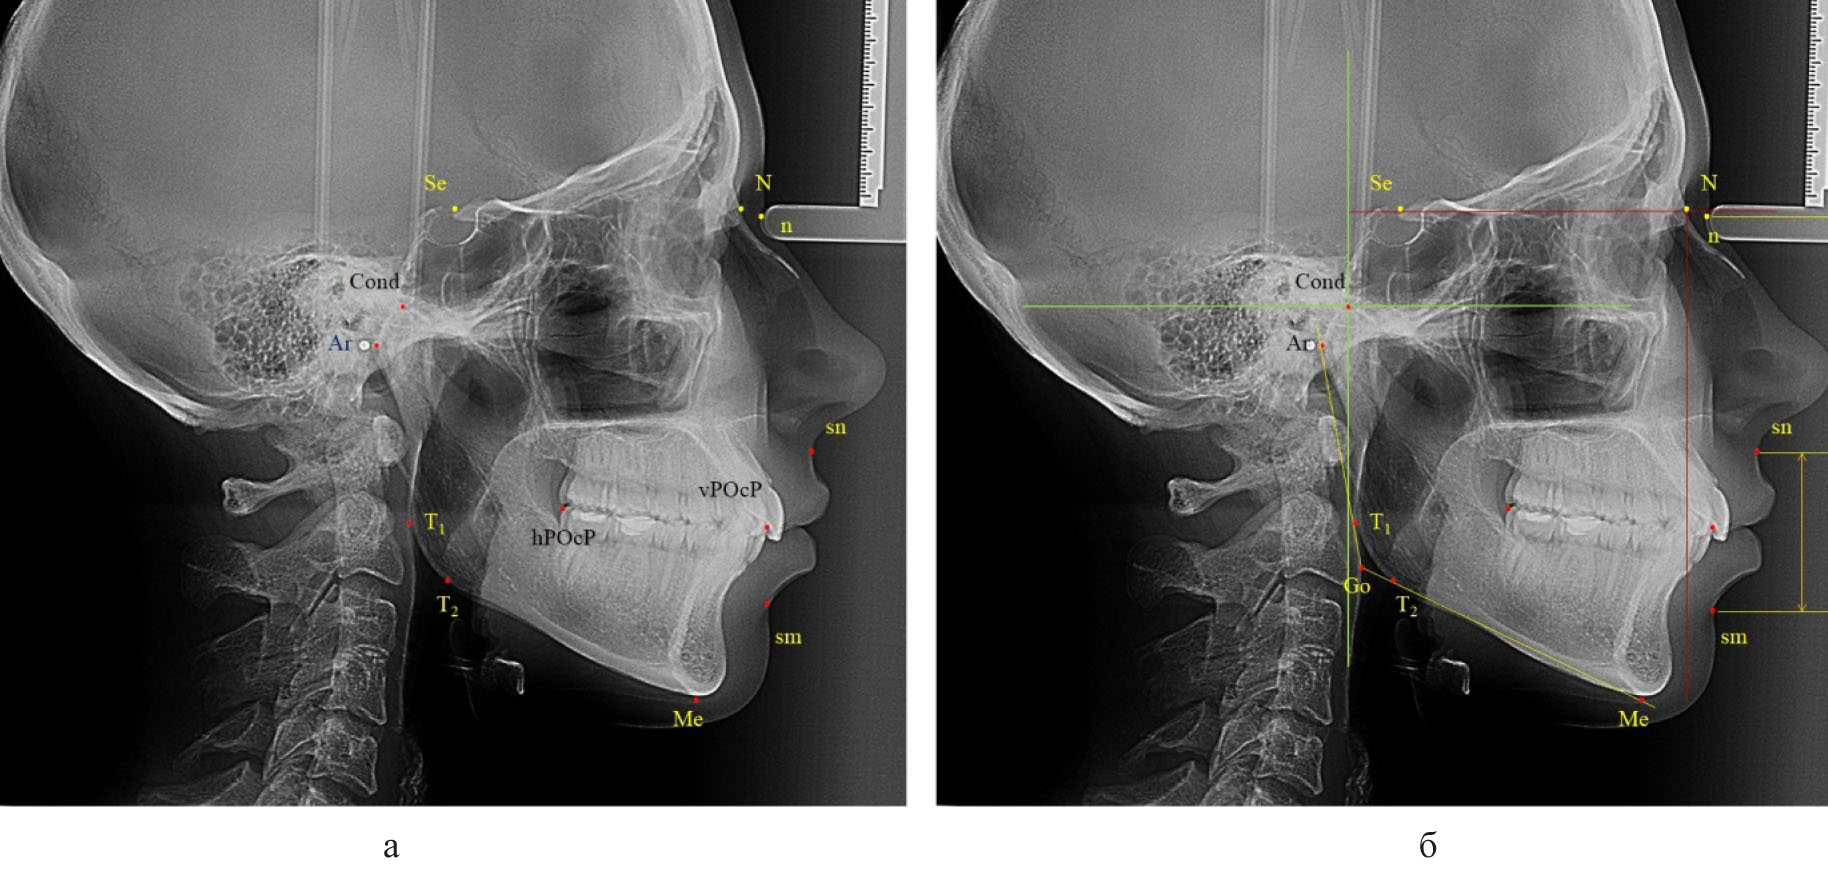

На телерентгенограммах, масштабированных 1 : 1, наносили основные точечные ориентиры. Из многообразия общепринятых в клинической стоматологии точек использовали точки, позволяющие в последующем оценивать вертикальные размеры лицевой области, положение элементов сустава и окклюзионные ориентиры. Для определения положения плоскости основания черепа использовали среднюю точку входа в турецкое седло (Se), которую соединяли с точкой соединения лобной и носовых костей (N), как было рекомендовано A.M. Schwarz (1958). Перпендикулярно к ней из назального костного ориентира опускали линию (прототип вертикали Дрейфуса), которая позволяла определять положение верхней челюсти относительно структур черепа в целом. Кроме этого из костных ориентиров использовали верхнюю точку суставной головки (Cond), заднюю окклюзионную точку (hPOcP), расположенную на дистальном бугорке второго моляра, и переднюю окклюзионную точку (vPOcP) в месте смыкания антагонирующих медиальных резцов. Соединение указанных точек определяло расположение окклюзионной линии (плоскости). Из кожных ориентиров использовали назальную точку (n), субназальный ориентир (sn) и супраментальную кожную точку (sm). Для удобства измерений через указанные кожные точки проводили горизонтальные линии перпендикулярно к вертикали Дрейфуса и измеряли вертикальные размеры лица, в частности «n-sn» и «sn-sm» (рис. 1).

Рис. 1. Некоторые точки (а) и линии (б) для анализа боковой телерентгенограммы

Учитывая вариабельность вертикальных размеров лицевой области, обусловленных типом роста челюстей и лица, после получения абсолютных величин нами оценивались относительные показатели, в частности отношение размеров назального комплекса («n-sn») к межчелюстной вертикали («sn-sm»). Также оценивали положение окклюзионной линии к вертикали Дрейфуса и другим линейным ориентирам, принятым в стоматологии, в частности к Камперовской горизонтали, нижнечелюстной (мандибулярной) линии.